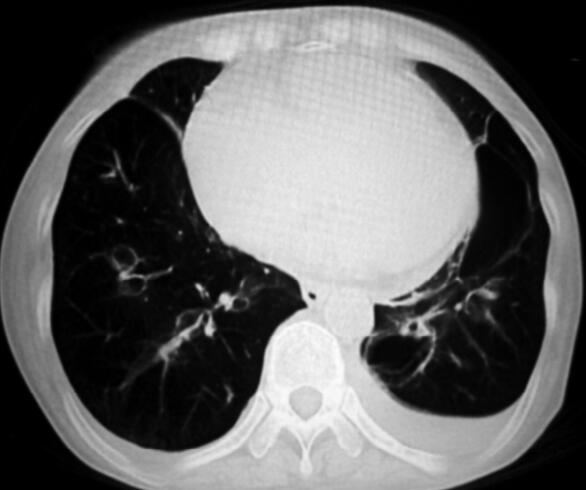

患者咳嗽咳痰、呼吸困难症状明显缓解,无发热,查体:球结膜无水肿,口唇无发绀,双肺偶可闻及少量湿啰音,四肢无水肿。复查血气分析(未吸氧):pH 7.36,PaO2 68mmHg,PaCO2 50mmHg,30.1mmol/L。患者病情已好转,考虑可以出院。复查胸部CT,肺大泡较前缩小(图3)。

图3

3.有肺气肿和多发肺大泡的病史,具有气压伤高危因素的患者行NPPV治疗时,呼吸机参数的调节应该仔细权衡利弊,不能完全根据指南推荐采用“患者可以耐受的最高吸气压法”来调节,应该以最小的吸气压力来满足临床治疗的需要。本病例中,患者出现了肺大泡的增大,应该与我们所设置的吸气压较高有关。